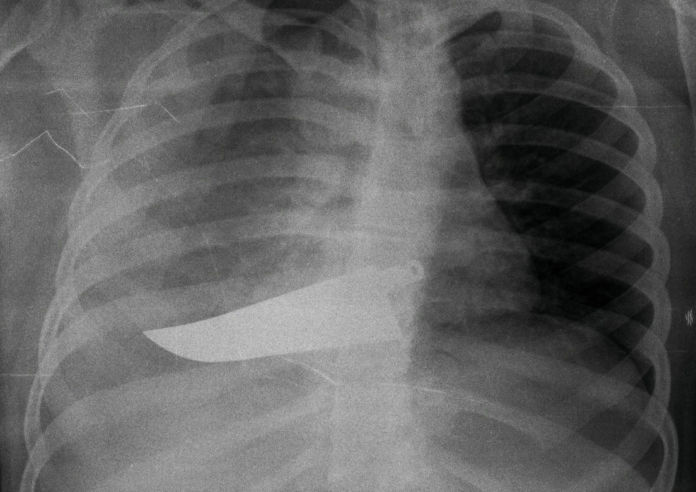

Bacini fratturati, tibie spezzate, clavicole staccate, falangi martoriate. Sono ciò che mostrano le radiografie appese nell’atrio dell’Ospedale Santi Paolo e Carlo di Milano, all’interno della mostra L’invisibilità non è un superpotere, allestita con l’obiettivo di dimostrare quanto la violenza sulle donne sia un fenomeno ancora sommerso, spesso celato dentro le mura domestiche e perpetrato da uomini vicini alle vittime, mariti, compagni e quasi sempre parenti. A fianco, gli scatti di Marzia Bianchi, che ha raccolto e interpretato tramite la fotografia alcune testimonianze riportate da quelle donne finite al pronto soccorso con gravi lesioni per le violenze subite. “Spesso le donne che giungono in pronto soccorso, non sapendo ancora nominare ciò che loro è accaduto, non dichiarano di aver nell’immediatezza di aver subito violenza”, riporta Maria Grazia Vantadori, Chirurga Referente per il Centro Ascolto e Soccorso Doona – CASD – del pronto soccorso Santi Paolo Carlo e ideatrice della mostra. “Questo ha un nome: Sindrome di Procne. Però i corpi, le lesioni parlano per loro e raccontano di vertigini di orrore quotidiano. Chi accoglie deve saper decodificare i silenzi, attribuire la giusta dimensione alle lesioni incompatibili con quanto narrato”. La mostra, supportata da Fondazione Pangea Onlus e da Reama, rete per l’empowerment e mutuo aiuto della stessa onlus, si pone l’obiettivo più difficile: rompere il silenzio. Vergogna, paura, solitudine e persino senso di colpa sono, infatti, le problematiche più grandi che ostacolano la battaglia globale per l’eliminazione della violenza sulle donne. Riconoscere e, di conseguenza, denunciare la violenza ricorrente, è ancora per tante un atto difficile e rischioso. Se poi, oltre alla famiglia e alla dipendenza psicologica, si aggiunge quella finanziaria, la reticenza a denunciare aumenta. Rete Reama coglie, con questa iniziativa, l’occasione per sottolineare l’importanza del lavoro in rete come strumento per l’intera società, per denunciare, contrastare e uscire, appunto, dall’invisibilità.